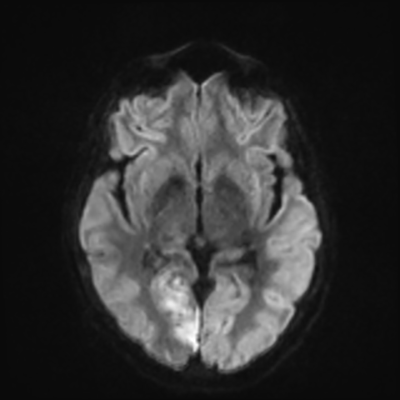

MRI brain (DWI)

MRI brain (DWI) 2/24 2/24

You can clearly see diffuse cortical and basal ganglia diffusion restriction, and that of his deep cerebellar nuclei as well. The right occipital lobe abnormalities are a little more prominent, but then you remember that he is known to have had a right occipital stroke weeks ago.

In reviewing his data, you know that he doesn't have any of the strong predictors of a poor neurologic prognosis. However, based on these findings on MRI, along with the absent reactivity on cEEG, you are able to tell the primary team and the patient's family that he is likely to have a poor prognosis, based on these multiple moderate predictors. Recovery is not completely impossible-- there is more uncertainty with this prognostication than if we were able to get SSEPs-- but you're very worried about his outlook and that any potential recovery would require a very protracted rehabilitation period. Given his high cervical cord injury level, tracheostomy would be required anyway. So, it comes down to whether his family thinks he'd want to pursue these aggressive measures.